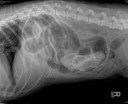

Cas intrigant – 1